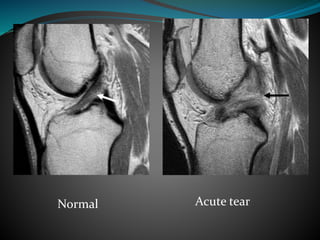

ACL Tear

Acute-

 Replacement of normal striated appearance by cloud

like high signal intensity

 Discontinuity of ligament and fibres don’t go parallel to

intercondylar roof

Normal Acute tear

Discontinuous fibres non visible fibres